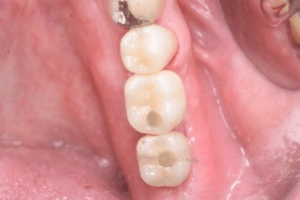

口腔内写真

- Befor

- After

| 年齢 | 50代・男性 |

| 主訴 | 左下7番 |

| 治療内容 | 右下7番インプラント埋入 |

| 治療費 | 合計:572,000円 診断料:55,000円 埋入料:165,000円 サージカルガイド:55,000円 静脈内鎮静麻酔:77,000円 仮歯:55,000円 上部構造(フルジルコニア):165,000円 (2023年1月現在) |

| 治療期間 | 約8ヶ月 |

| 治療方針 | 骨が十分にあるため、骨造成をすることなく埋入した。かみ合わせが強いので、負荷がかからないよう、夜寝るときにマウスピースをつけるよう指示をした。 |

| 担当者所見 | 左下6番7番のインプラントは他院で埋入しており、右下7番は抜歯したままで、かみ合わせの歯が落ちてきてしまうのでインプラントを埋入しました。 |